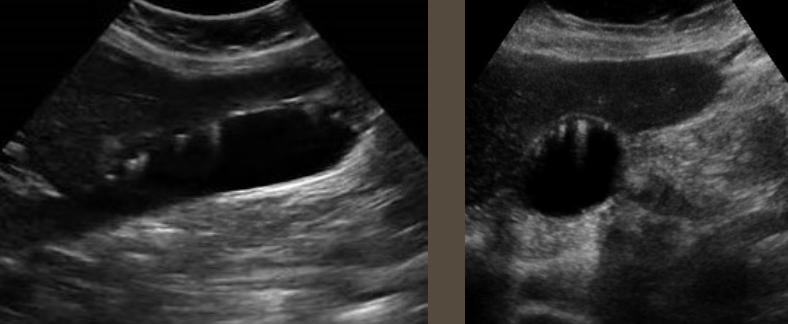

Cholelithiasis → stone in GB

clinical hx: 5 Fs (fat, fourty, female, fertile, fair)

s/sx: commonly asymptomatic, RUQ pain after eating greasy/heavy foods, GB attack/referred pain → right shoulder, back, & sternal chest pain

2D US: well-defined echogenic foci in dependent part of GB producing dark posterior shadowing (stones under 3 mm may not produce shadow), WES sign = wall-echo-shadow sign indicating multiple stones/one large stone, mobile w/ patient positioning

color doppler: avascular

DDX: GB sludge (tumefactive), polyp